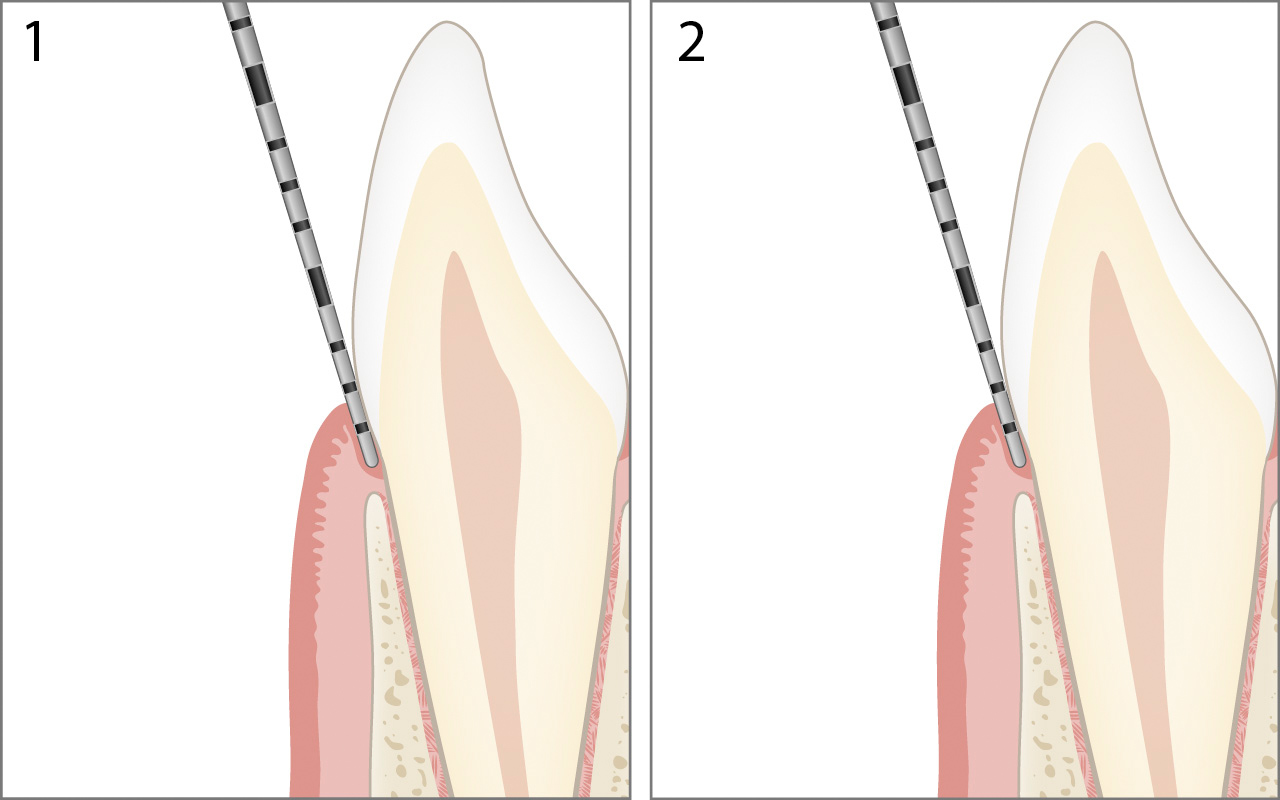

Gesundes Parodont

Im gesunden Parodont liegt die Schmelz-Zement-Grenze unterhalb des Gingivalrandes und unmittelbar über dem Attachmentniveau (kein Attachmentverlust).

Die Werte für "Margo Gingivae" 1 und "Sondierungstiefe" 2 sind in diesem Fall identisch.

Die Berechnung des Attachmentniveaus in der oben gezeigten Abbildung lautet:

Attachmentniveau 0mm = Sondierungstiefe 2mm – Margo Gingivae 2mm